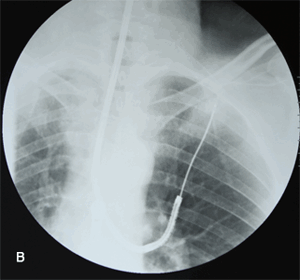

Рис. 4. Фибробронхоскопия больного М., 59 лет с центральным раком левого легкого. Опухоль распространяется на трахею и хирургически неудалима. Для восстановления и поддержания просвета дыхательных путей в нашем Центре больному установлен саморасправляющийся стент в трахею, после чего пациент направлен на химиолучевое лечение.

Рис. 6. Видеомедиастиноскопия - диагностическая операция, по результатам которой выбирается тактика лечения, определяется целесообразность хирургического лечения. А - введение медиастиноскопа в средостение через маленький разрез кожи на шее. Б - выполнение биопсии лимфоузлов под контролем видеоизображения. В - эндоскопическая картина во время операции: 1 - левый главный бронх, 2 - правый главный бронх, 3 - бифуркационные лимфоузлы, 4 - легочная артерия. Г - операция завершается наложением косметичного внутрикожного шва, практически незаметного на коже.